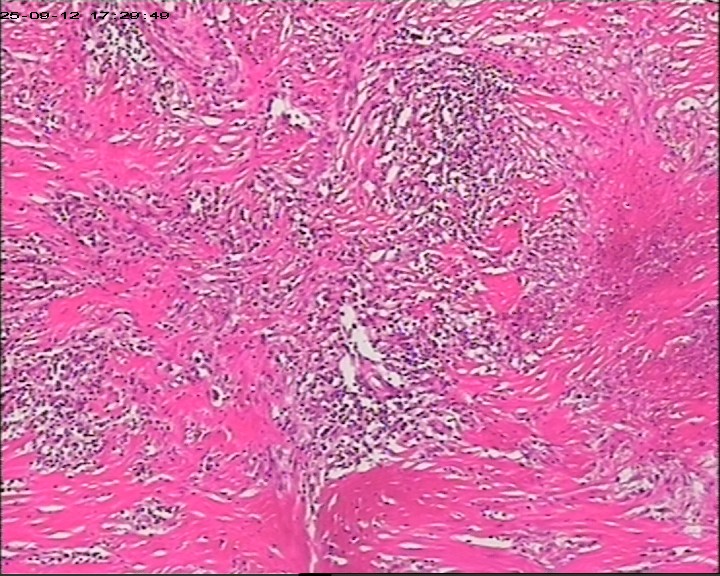

性别年龄47岁临床诊断肝占位性质待查,肝棘球蚴病?

大体所见肝组织一块,大小为20*18*15cm,切面多房囊性,部分内含坏死样物。

建议:描述性病理诊断!(感觉符合棘球蚴病病理改变,但未见明显的直接证据!)

大体检查有没有看到粉皮样的角质膜?取角质膜在镜下找到头节有助于诊断。